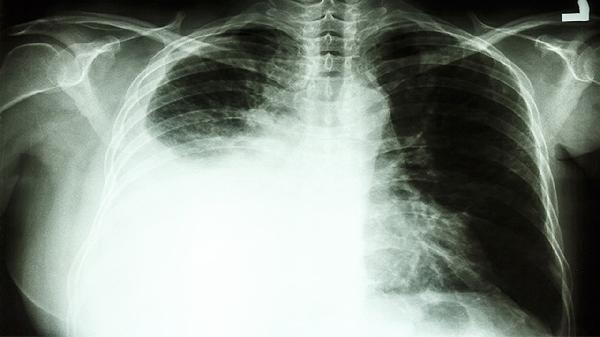

当这些症状单独出现时,确实可能与其他疾病混淆。但如果同时具备2-3项表现,特别是长期吸烟、有肿瘤家族史的人群,建议尽快做低剂量螺旋CT检查。现代医学已经证明,早期肺癌的五年生存率可达80%以上,关键就在于及时发现那些狡猾的"信号弹"。记住,身体从不会无缘无故闹脾气,给它多1点关注,就是给自己多一份保障。